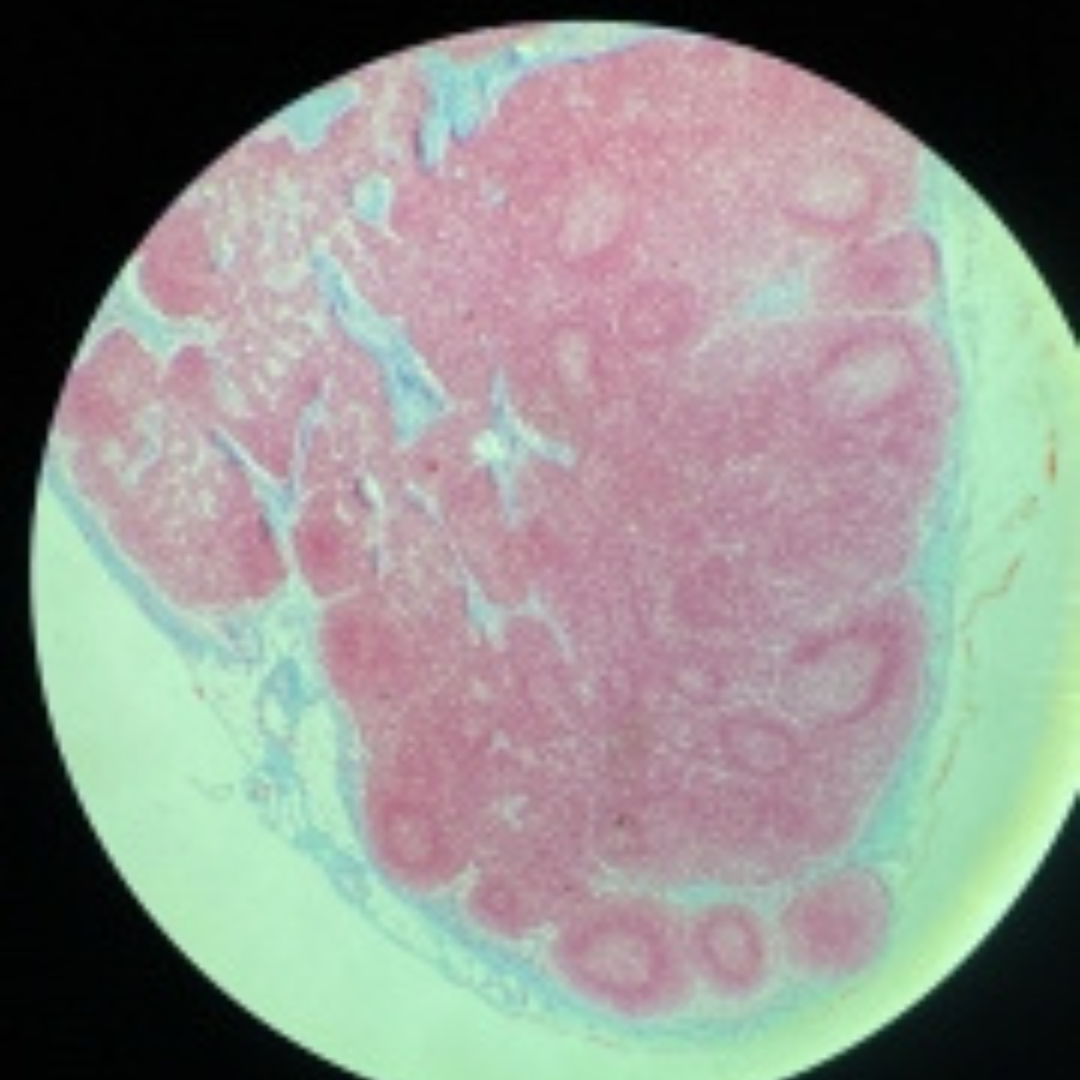

Lymph Node

11

New cards

Lymph Node

12

New cards

Lymph Node

13

New cards

Lymph Node

14

New cards

Lymph Node

15

New cards

Lymph Node